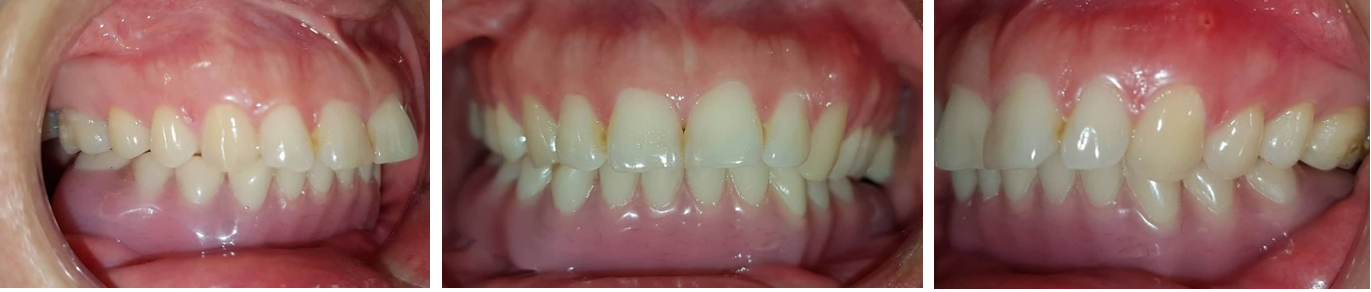

Phục hình sau cùng

Sau điều trị